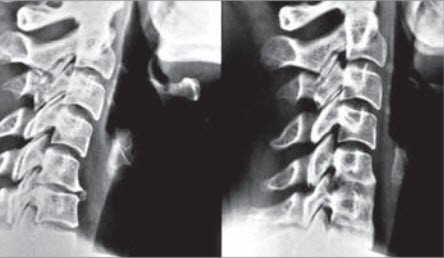

A: Gelenk normal, rechts arthrotisch verändert

B: Die Verschraubung führt zu Schmerzlinderung